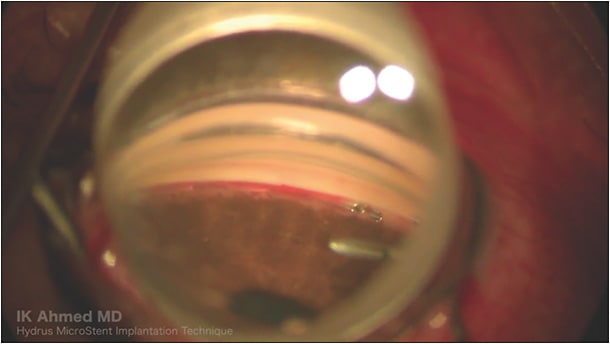

Roughly the size of an eyelash, the Hydrus Microstent is a device made from nitinol, a super-elastic, biocompatible alloy, which is designed to lower intraocular pressure (IOP) by acting within Schlemm’s canal.1 At 8 mm in length, the Hydrus is curved to match the contour of Schlemm’s canal with alternating “spines” and “windows” to provide structural support while facilitating aqueous humor outflow pathways respectively. It is implanted using an ab-interno, clear-corneal approach with the implant designed to cover 3 clock-hours of Schlemm’s canal. The innovative trimodal mechanism of action works by maximizing flow through an inlet structure, creating a scaffold that dilates Schlemm’s canal to bypass resistance and enhances aqueous flow through conventional outflow systems. The device provides direct flow into the canal through the inlet and stretched inner wall, thereby enhancing the effective filtration area, as well as maintaining the patency of the canal to provide flow in collector channels and aqueous veins.